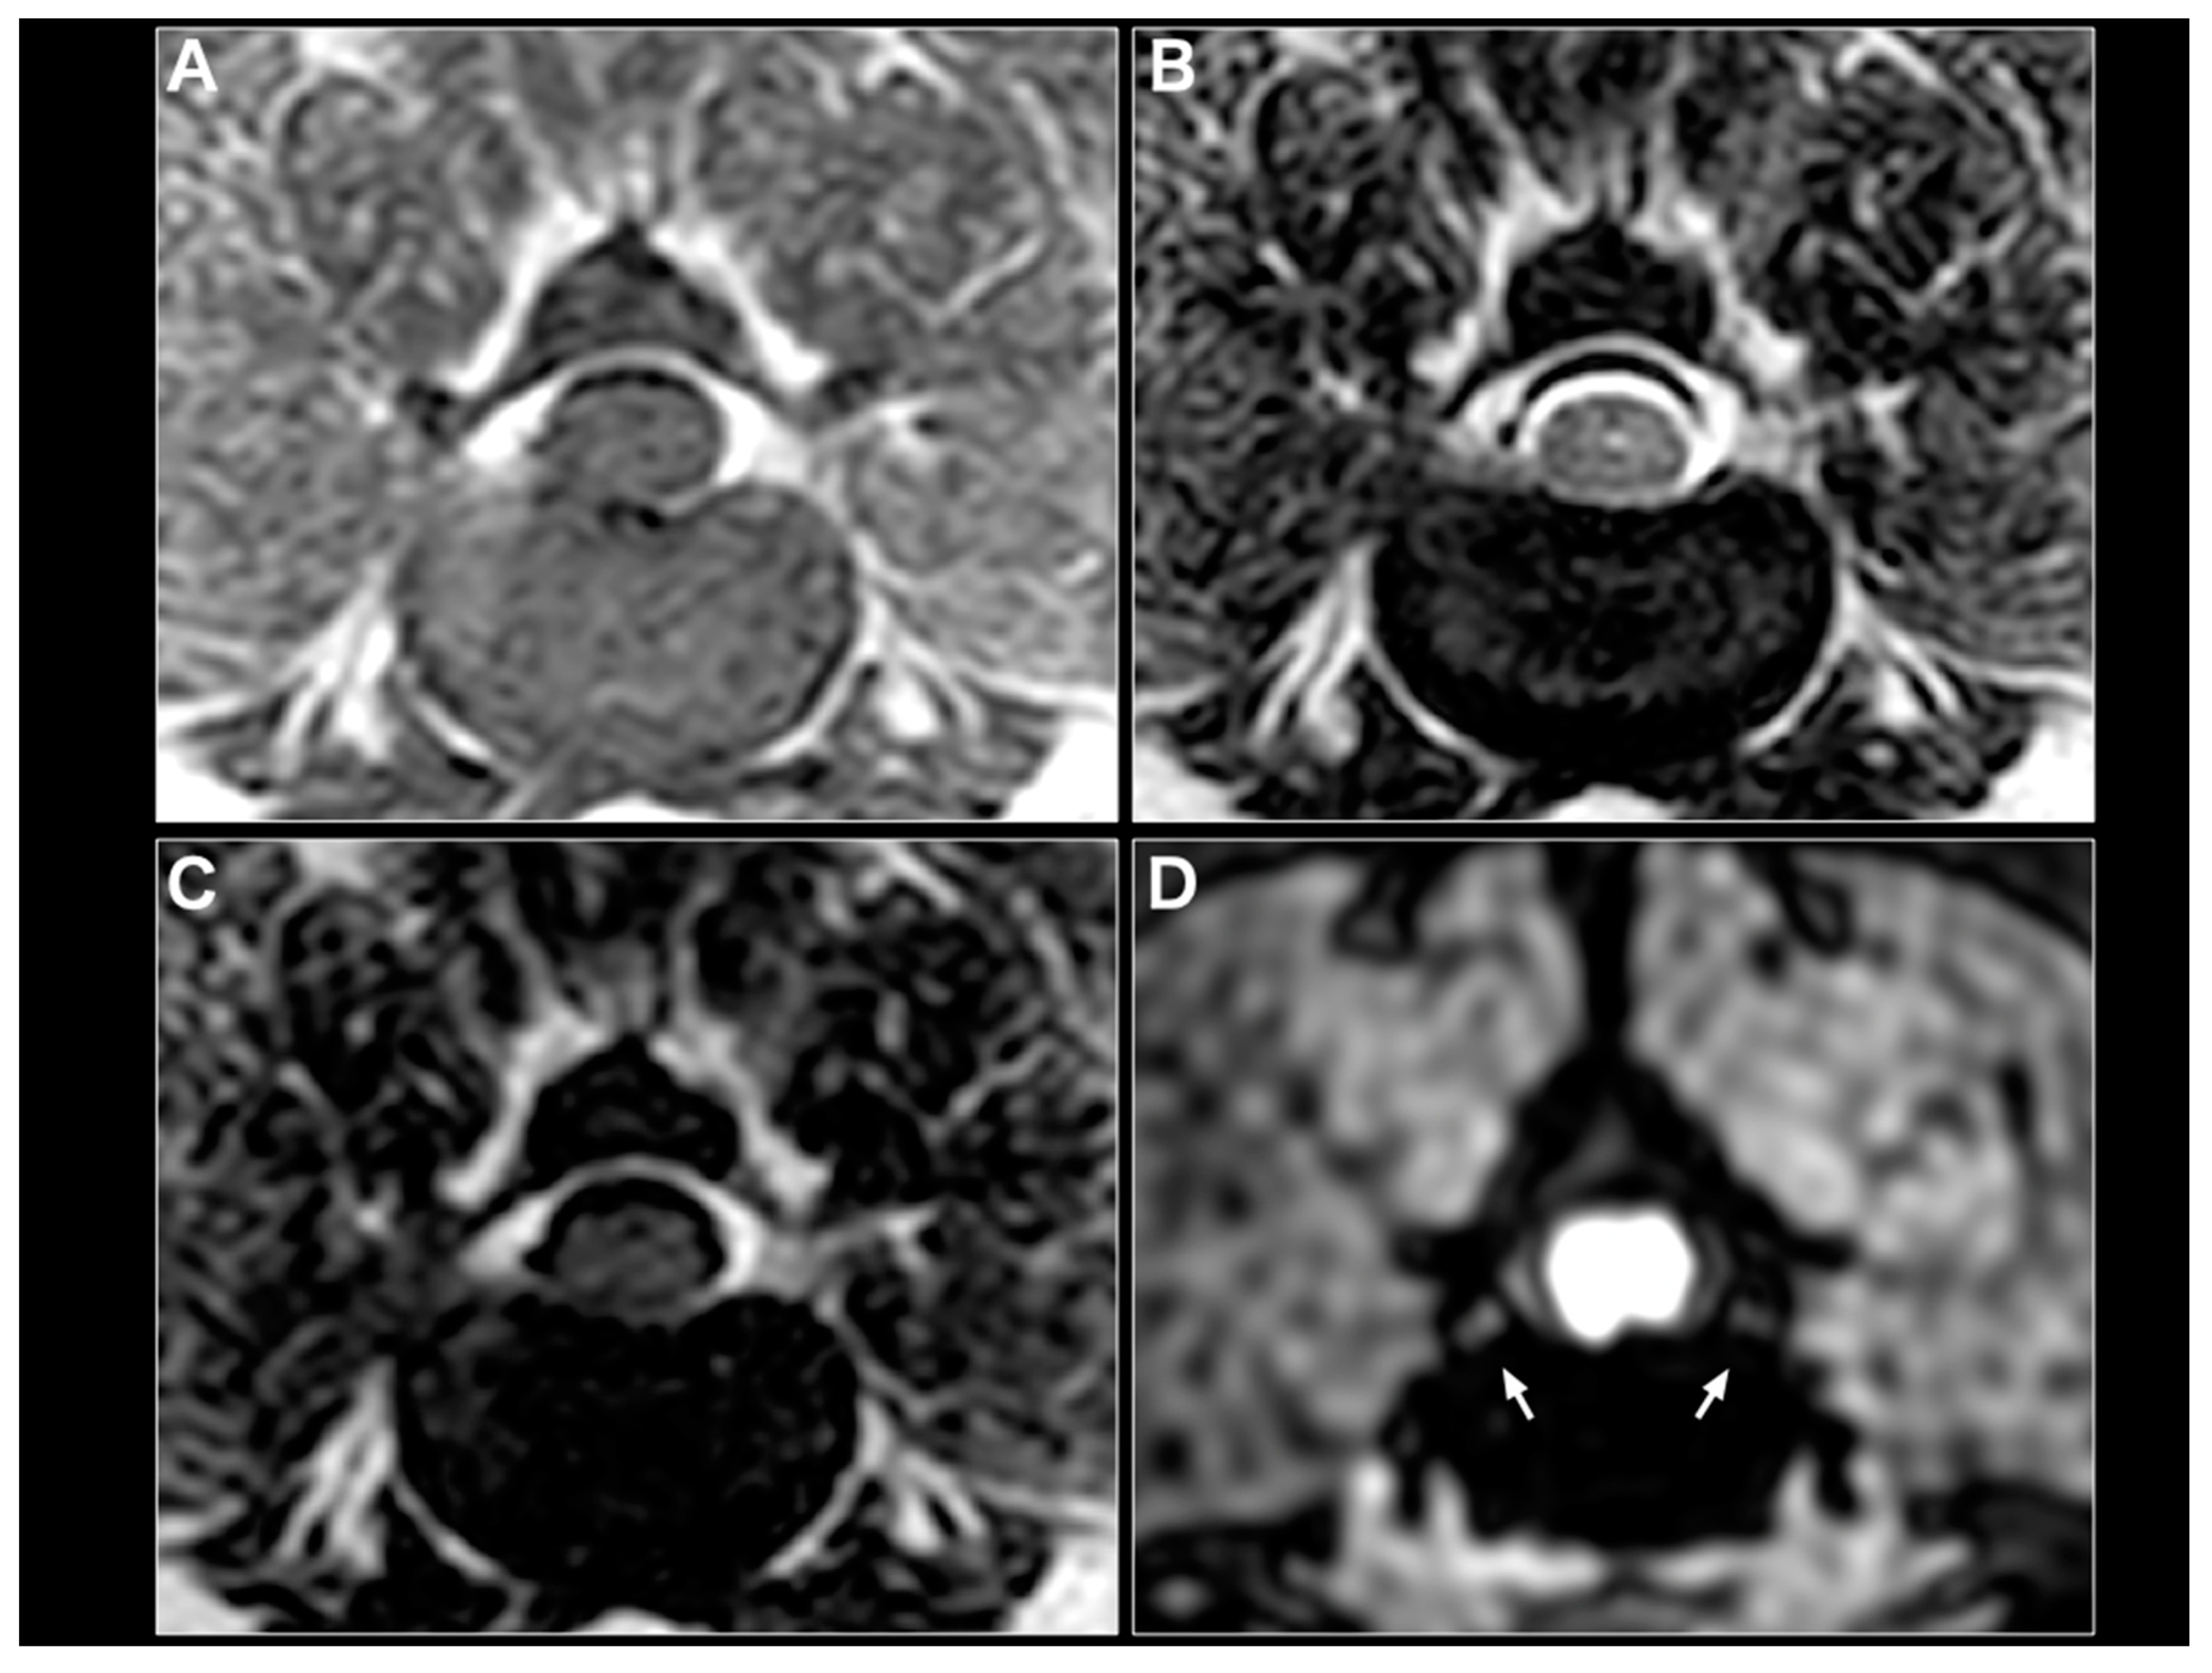

2.2. MRI Sequences

2.3. Image Analysis